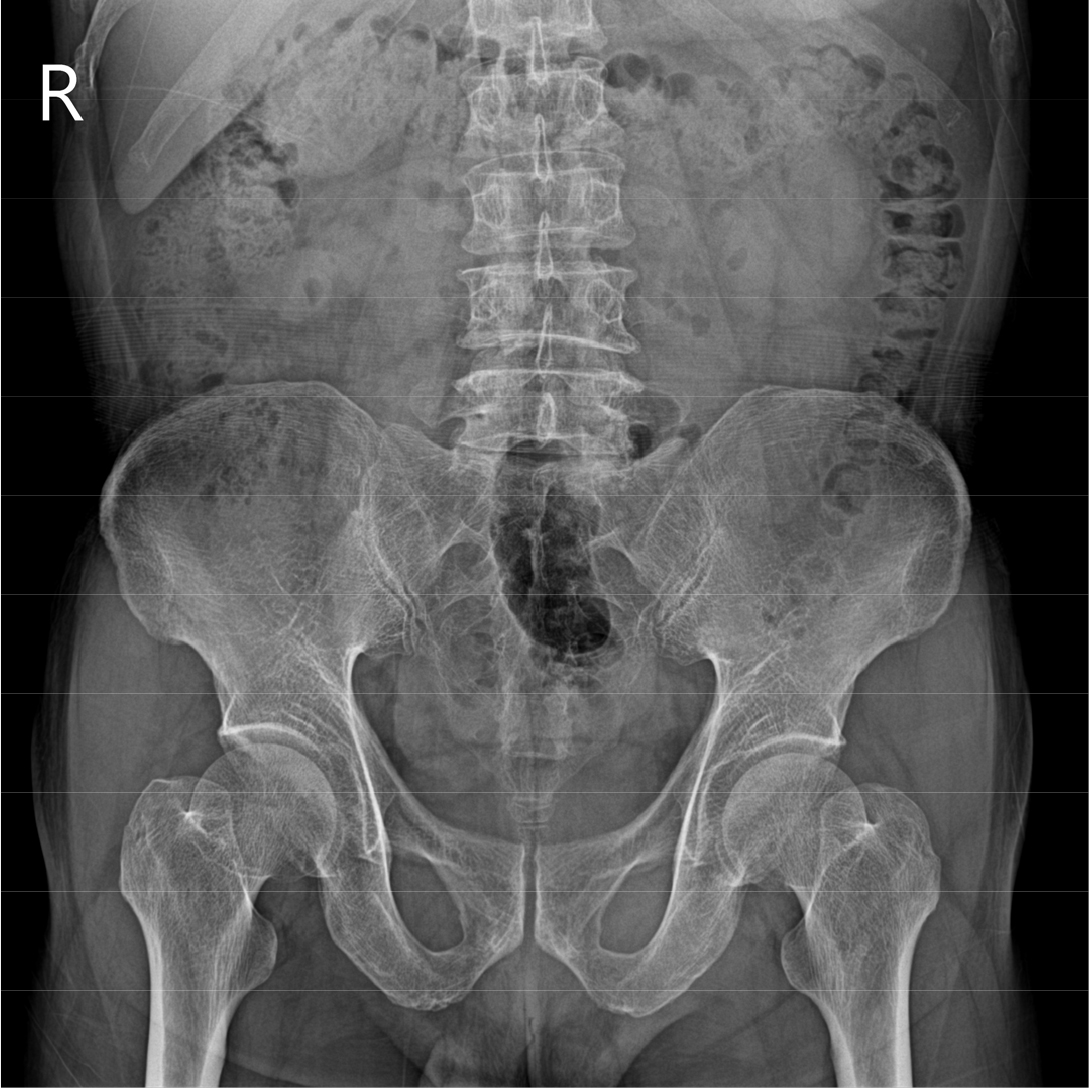

[그림 1] KUB에서 병변과 연관된 특이 소견은 관찰되지 않았다.